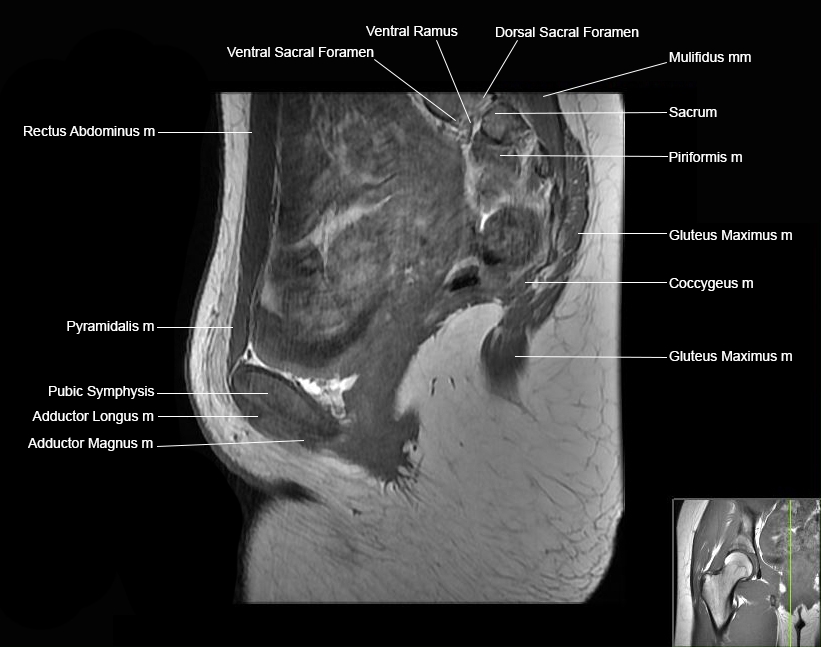

MRI Hip Anatomy

Scroll using the mouse wheel or the arrows